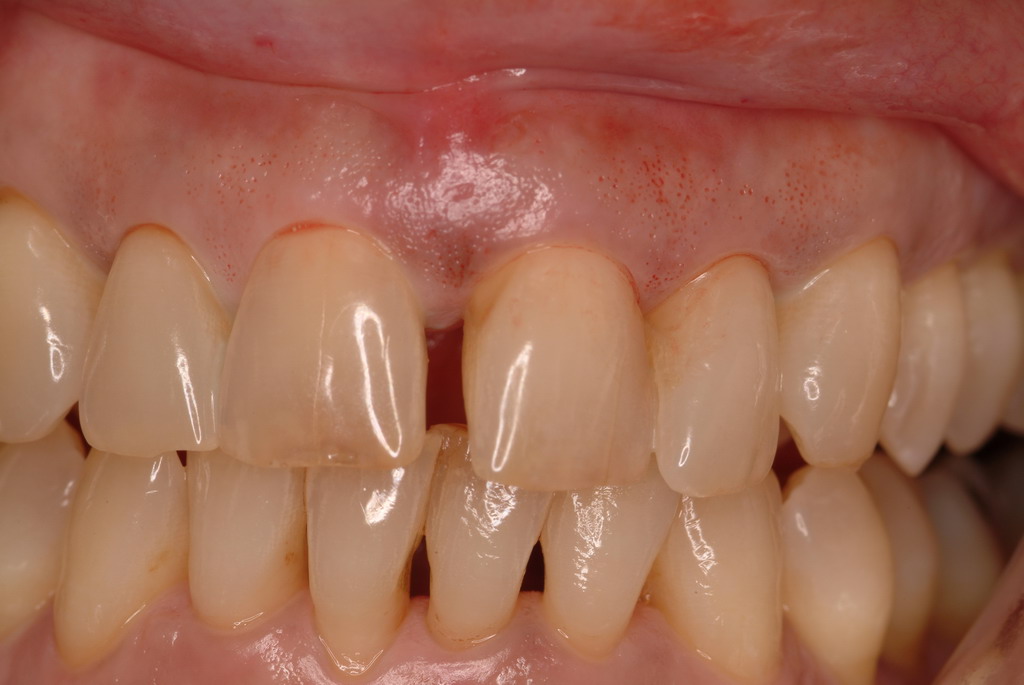

High-strength ceramic materials can be used in select cases to fabricate resin-bonded bridges to replace missing teeth as an alternative to removable prostheses or more invasive procedures such as conventional bridges or dental implants. The two missing lower central incisors (Figure 6) were replaced with two zirconia-based resin-bonded bridges (Figure 7). The single-retainer wing design has shown more than 94% clinical success after 10 years, which is significantly higher than the conventional two-retainer design (67.3% success).6 Proper bonding, however, is key for success and employs an air-particle abrasion step (Figure 8) followed by the application of a special ceramic primer (Figure 9). Figure 10 through Figure 12 demonstrate the clinical outcome.

Postoperative situation: left lateral view.

Figure 11

Postoperative situation: right lateral view.

Figure 12